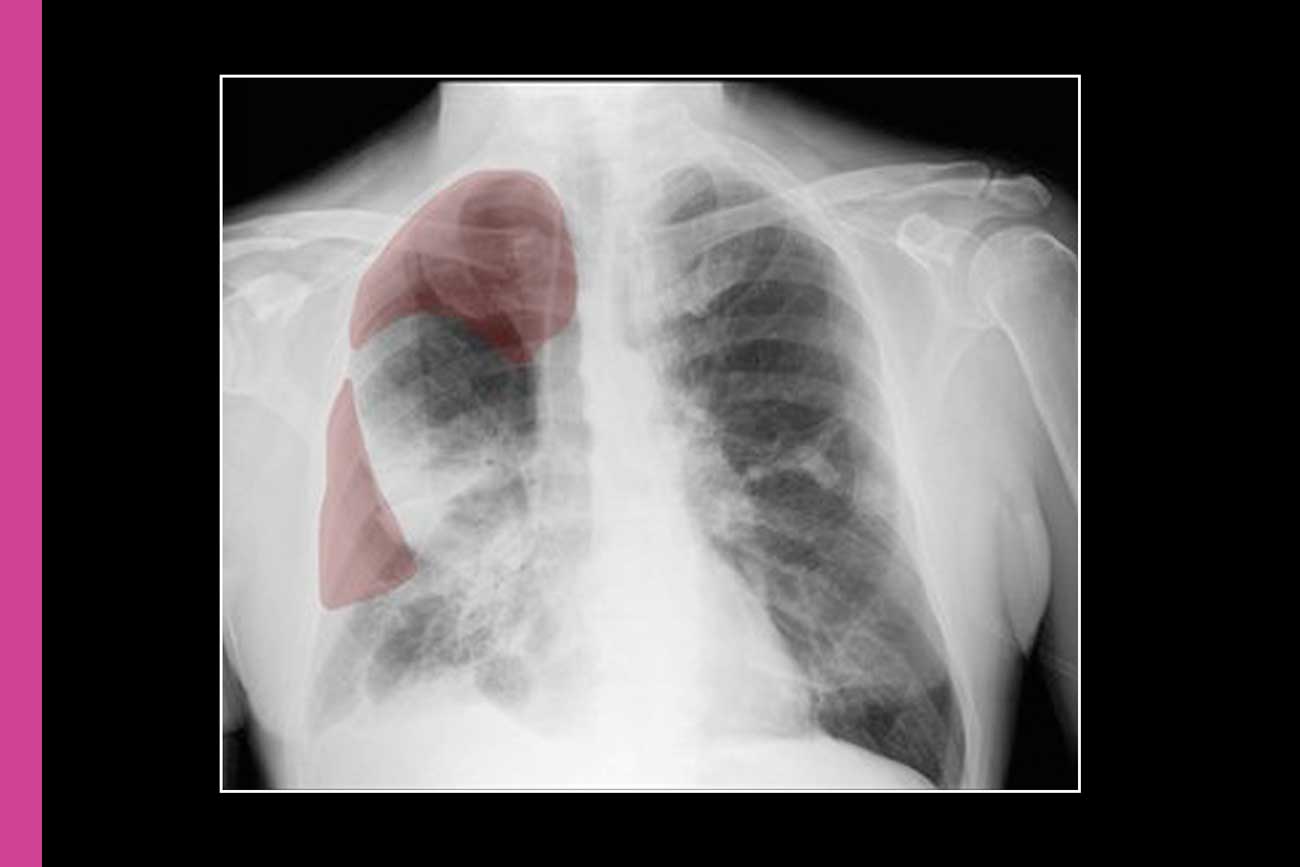

Tens of thousands of Americans suffer pneumothoraces, a type of collapsed lung, annually. The condition is caused by trauma or lung disease — and serious cases can be deadly if diagnosed late or left untreated.

This type of collapsed lung is difficult to identify: The illness can mimic others both in symptoms and in x-rays, in which only subtle clues may indicate its presence. Meanwhile, radiologists must interpret hundreds of images daily, and some hospitals do not have around-the-clock radiologists.

UCSF researchers created the first AI bedside program to help flag potential cases to radiologists. In 2019, the tool was the first AI innovation of its kind to be licensed by the U.S. Food and Drug Administration. Today, it’s used in thousands of GE Healthcare machines around the world.

Researchers from the Department of Radiology and Biomedical Imaging created a database of thousands of anonymous chest X-rays. Some of these images showed cases of collapsed lungs and others not. Next, researchers trained the AI tool on this database before testing it on thousands of other images to ensure it could flag potential cases accurately.

The AI screener works with portable X-ray machines, so doctors can use it right at a patient’s bedside without making major infrastructure investments.

“I think of this as an additional safety check that can deliver diagnoses and patient care sooner,” explained associate chair for Translational Informatics John Mongan, M.D., Ph.D., who codeveloped the AI algorithm with Radiology professor Andrew Taylor, M.D., Ph.D. Mongan is also a director of the Center for Intelligent Imaging.